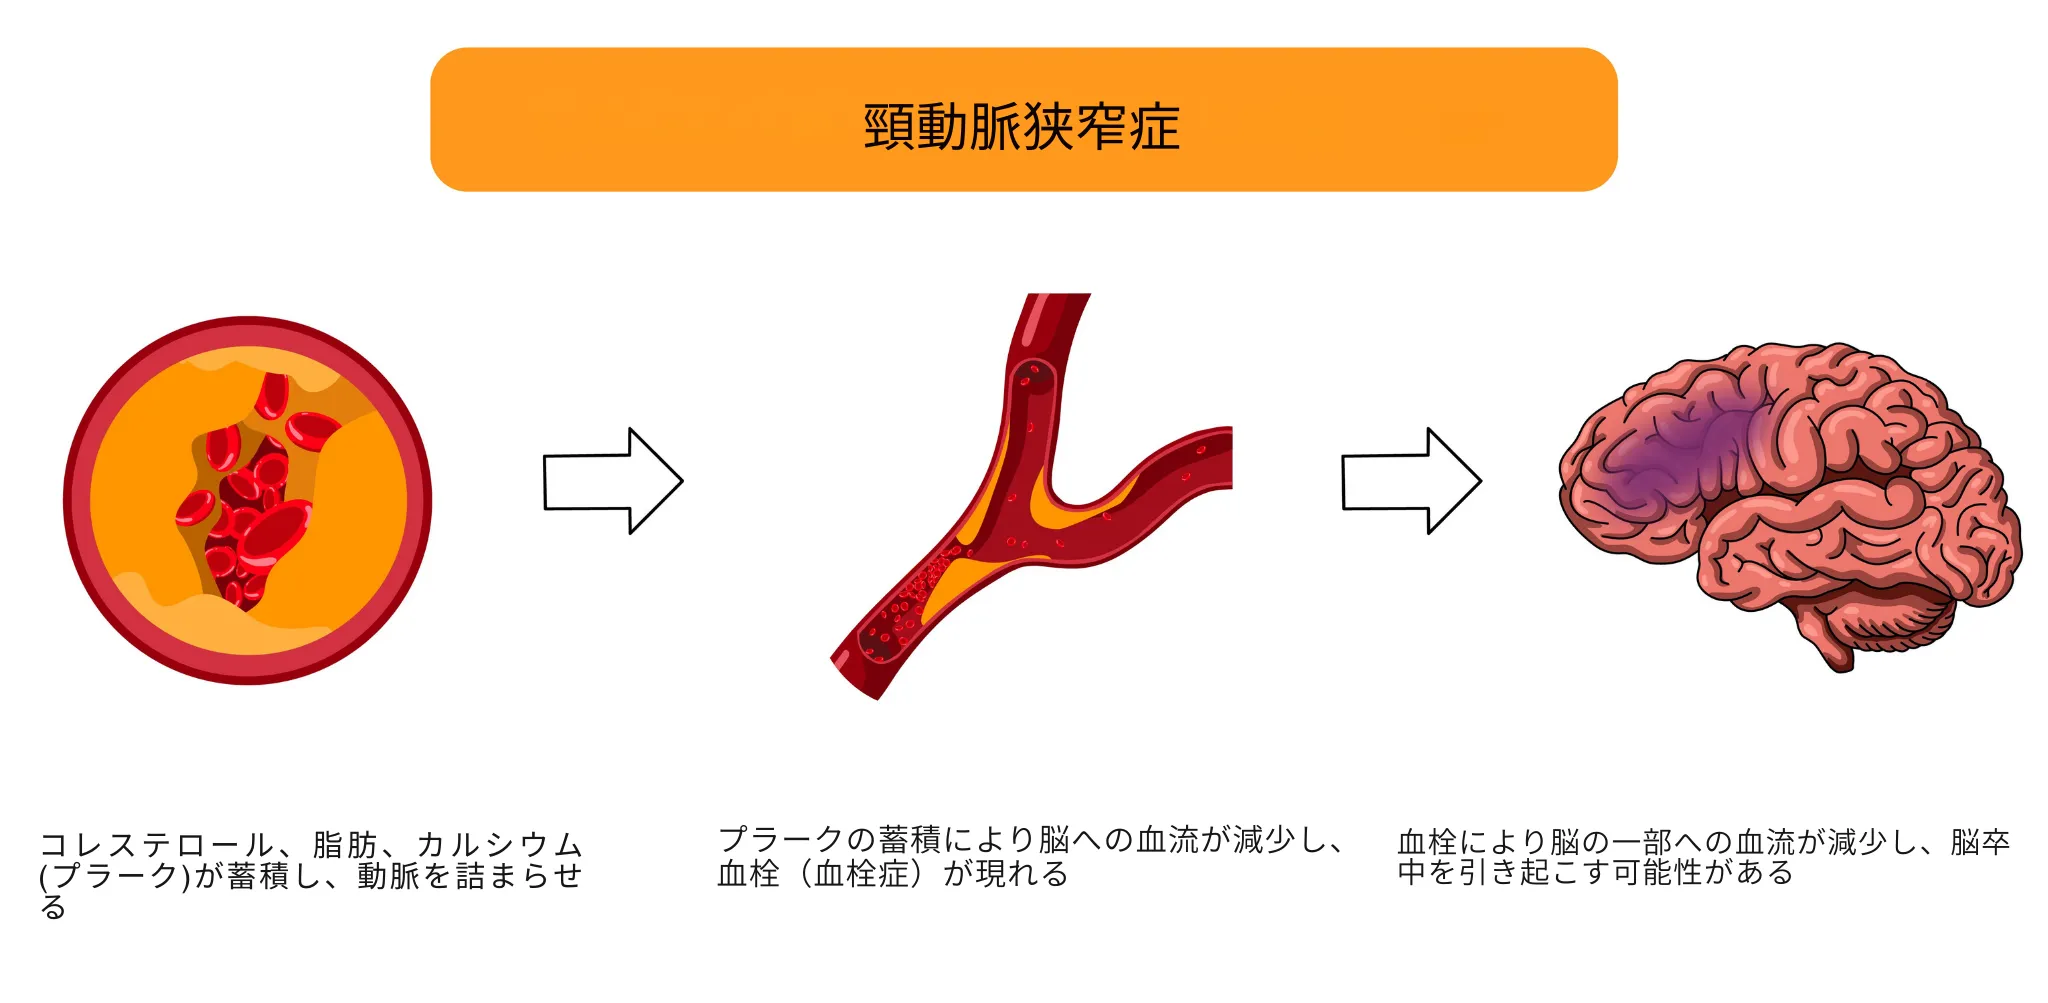

頸動脈狭窄症

頸動脈狭窄症は、脳に血液を送る首の動脈(頸動脈)が動脈硬化により狭くなる病気です。脳への血流が不足したり、狭くなった部分にできた血栓(血の塊)が剥がれて脳に飛んだりすることで、脳梗塞の原因となります。

自覚症状がないまま進行することが多いのが特徴ですが、一時的に手足のしびれ・脱力、言葉が出にくい、片方の目が見えなくなるといった症状が現れることがあります。これは「一過性脳虚血発作(TIA)」と呼ばれ、本格的な脳梗塞の前触れであるため、直ちに受診が必要です。

LEADと同様、糖尿病、高血圧、脂質異常症、喫煙が主なリスク因子です。首の血管に動脈硬化がある場合、心臓の冠動脈や足の血管も狭くなっている可能性が高いため、全身の血管の状態をあわせて確認することが重要です。